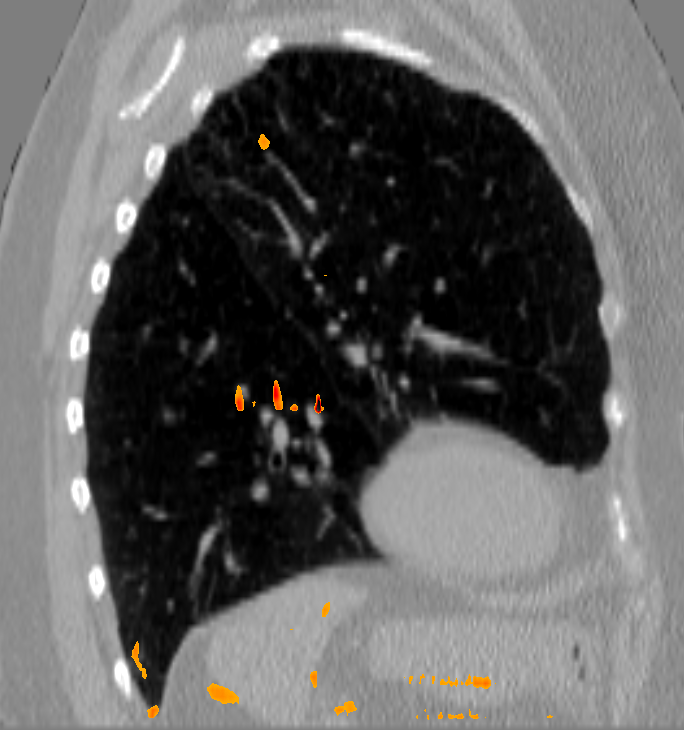

V-C 4D Evaluation

The initial average landmark distance between consecutive phase images was 2.25 ±plus-or-minus\pm 1.55 mm for the Popi datasets and 2.19 ±plus-or-minus\pm 2.02 mm for the DirLab datasets. The proposed registration algorithm could decrease the average distance to 1.24 ±plus-or-minus\pm 0.90 mm and 1.54 ±plus-or-minus\pm 1.31 mm, respectively. For a comparison with existing 4D registration methods we applied the publicly available method by [23] to the respiratory datasets and achieved average registration errors similar to the ones of our method: 1.56 ±plus-or-minus\pm 1.42 mm for the DirLab and 1.11 ±plus-or-minus\pm 0.87 mm for the Popi datasets. The construction of trajectories for voxels requires the combination of all DVF of a 4D dataset. As a consequence the registration error at the start of a trajectory gets propagated over time and increases or decreases with the combination of the different DVF. In Fig. 4 the error evolution is visualised for the three test datasets. At the beginning the mean registration error is 1.54 mm for the DirLab datasets and 1.24 mm for the Popi datasets. The error then increases to a mean of 2.58 mm for DirLab and 2.07 mm for Popi in the middle of the periodic motion. In the end of the breathing cycle the error falls to an error around 1 mm for both datasets. A similar error propagation pattern could be measured for the Sunnybrook datasets. For the Sunnybrook datasets segmentations are only available for the extreme phases, which allows only four comparisons per dataset. When starting with the end-diastolic phase a comparison in the middle of the cyclic motion to the end-systolic segmentation and in the end of the cycle motion to the original end-diastolic segmentation is possible. The same applies when starting with the end-systolic segmentation. In Fig. 4 the red dots indicate the measured DSC overlap, the red dotted line was fitted to the dots and estimates the DSC overlap for phase images without a segmentation available. Compared to a direct registration of the maximum exhale and inhale phases the registration error increased on average by 0.48 mm with the combination of the DVF. The average registration error for the extreme phases in the Popi dataset increased from 1.46 ±plus-or-minus\pm 1.59 mm to 1.98 ±plus-or-minus\pm 1.56 mm when we registered the whole 4D dataset instead of the two extreme phases solely. The same analysis reported an increase from 1.83 ±plus-or-minus\pm 2.35 mm to 2.54 ±plus-or-minus\pm 2.01 mm for the DirLab images and and decrease in the DSC from 0.86 ±plus-or-minus\pm 0.10 to 0.79 ±plus-or-minus\pm 0.14 for the Sunnybrook data. The DVF of the 4D evaluation showed a FoF of 0.02 % and an average Jacobi determinant of 1.00 ±plus-or-minus\pm 0.06.

Refer to caption a) before registration Refer to caption b) after registration

Figure 4: In this figure the development of the registration error over time is plotted for the different 4D datasets before a) and after registration b). In the beginning the error is low, then due to large deformations and the combination of deformation vector fields the error increases towards the middle of a time series until it decreases again because of the periodicity constraint. For the cardiac Sunnybrook datasets only segmentations for the 2 extreme phases are available, therefore we interpolated the remaining values (red line). The magenta filled area indicates the average registration error for the Popi and DirLab datasets ±plus-or-minus\pm standard deviation.